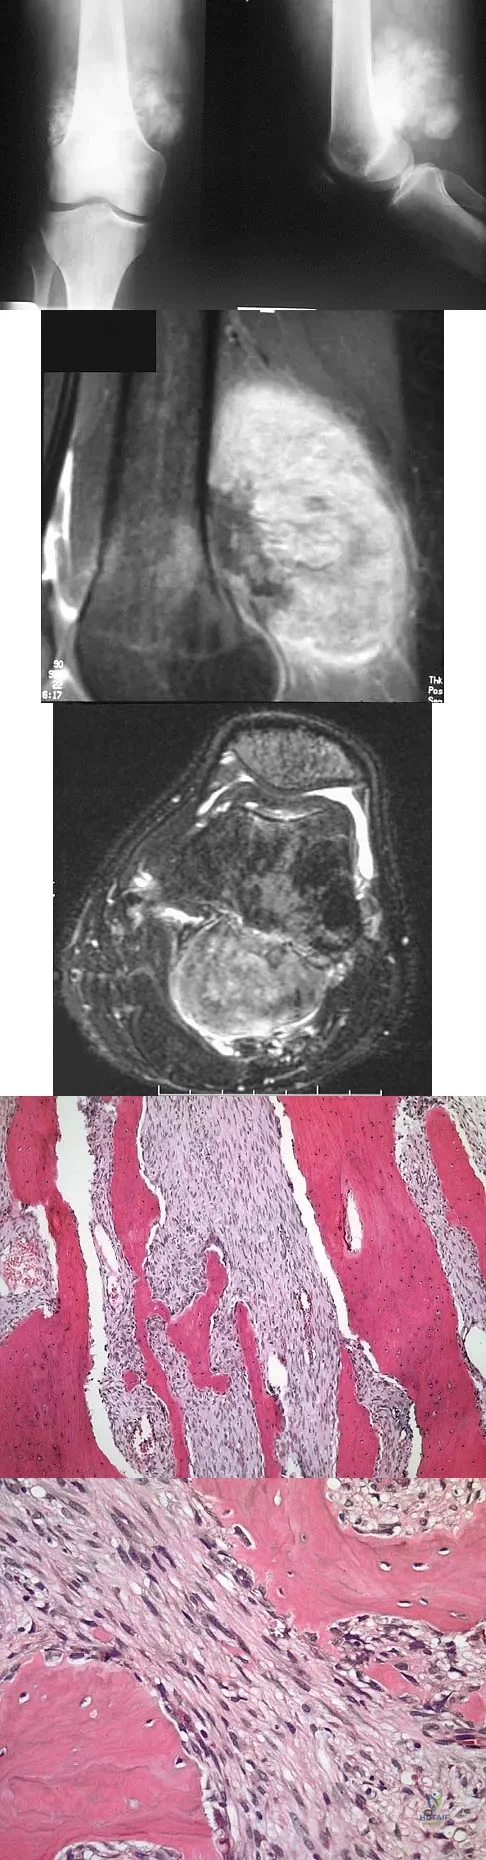

An 18-year-old boy has had pain in the right knee for the past 6 months. Examination reveals some fullness behind the knee but no significant palpable soft-tissue mass. There is no effusion, and he has full knee range of motion. The remainder of the examination is unremarkable. A radiograph and MRI scans are shown in Figures 33a through 33c, and biopsy specimens are shown in Figures 33d and 33e. What is the most likely diagnosis?

Explanation